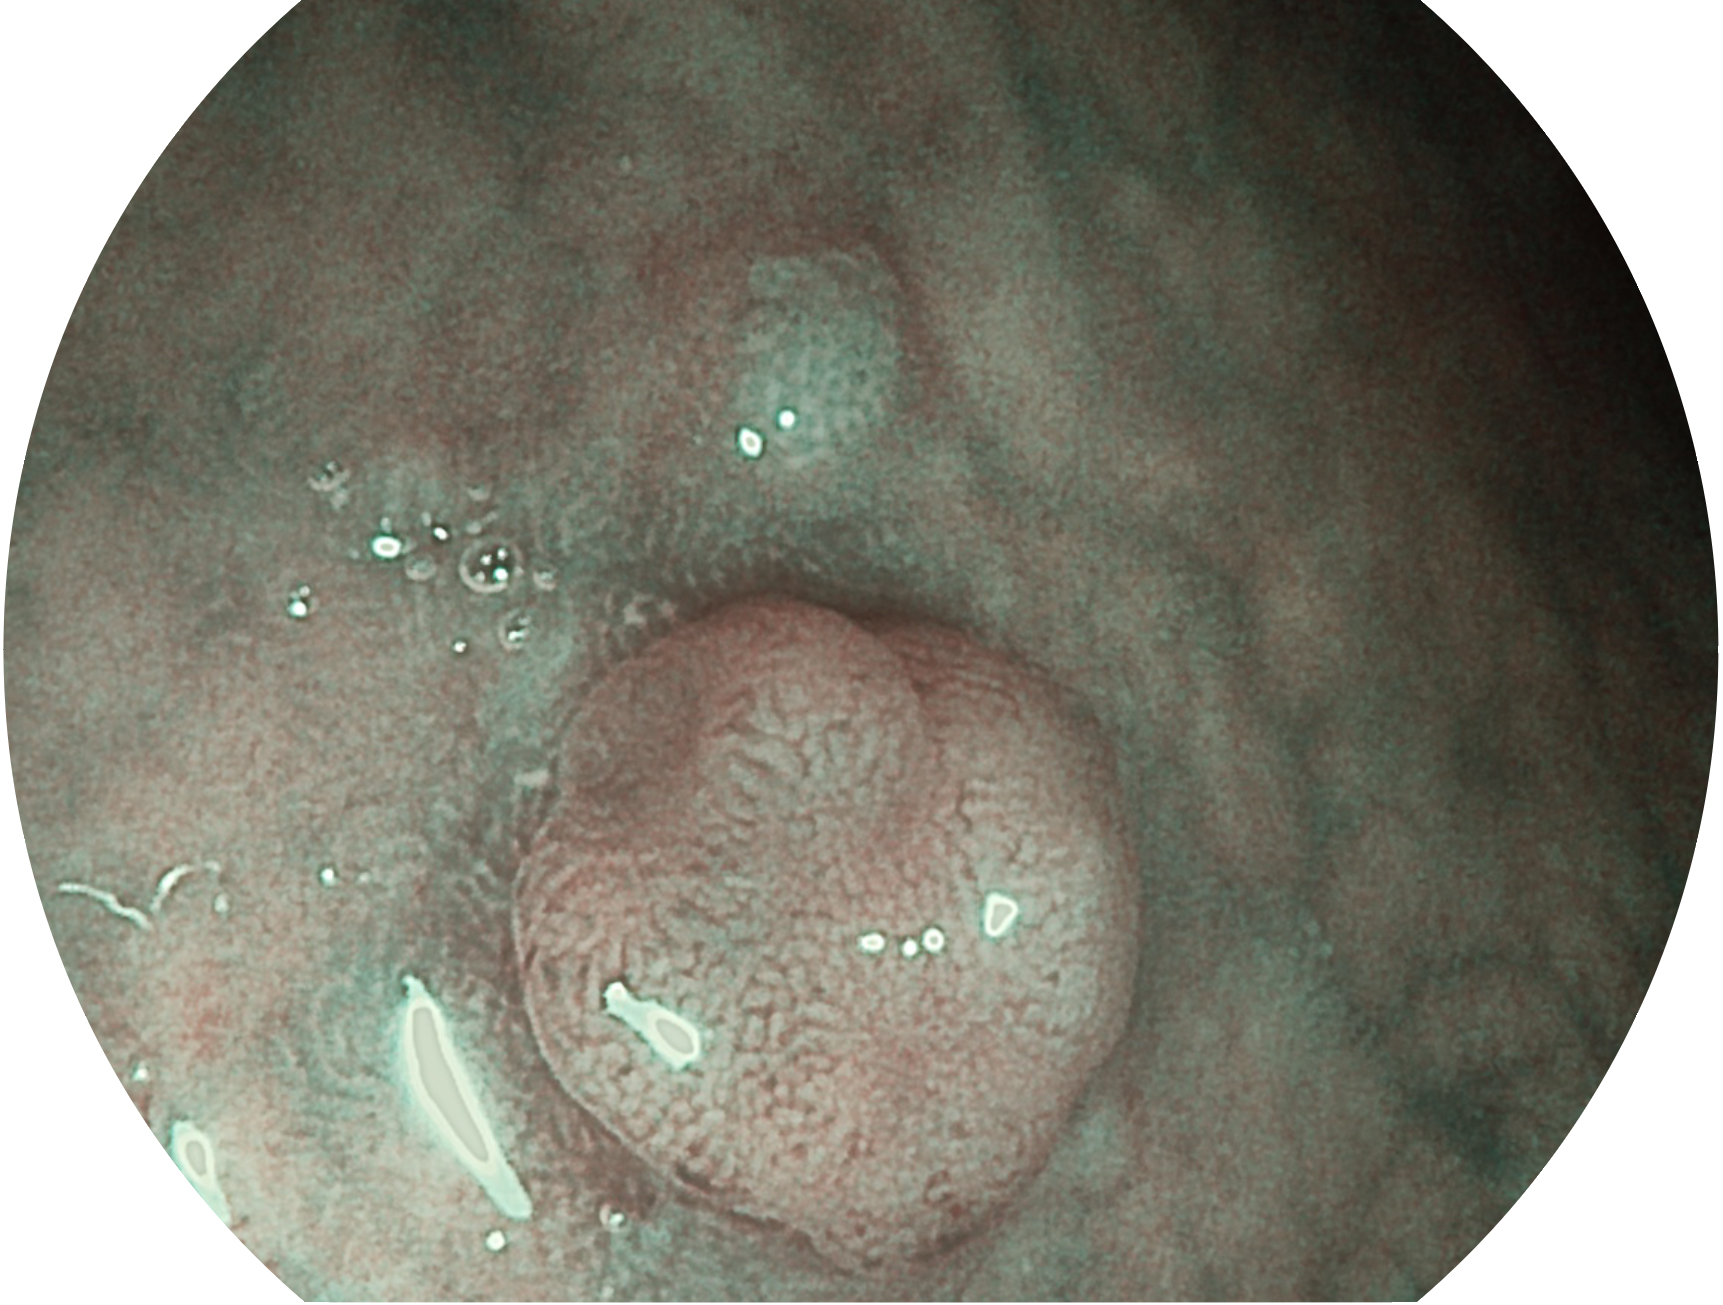

開立新開發(fā)的內(nèi)鏡染色技術(shù),主要是基于多波長LED 光源的開發(fā),VLS-55Q 四波長LED 光源是由四個不同顏色的LED光按照相應(yīng)照明模式所規(guī)定的特定發(fā)光比例進行合束后形成,合束后形成的照明光的光譜由紅光、綠光、藍光及藍紫光這四個不同的波段范圍構(gòu)成。具有更高光譜自由度,通過光譜比例的控制,實現(xiàn)了聚譜成像技術(shù),英文全稱為“Spectral Focused Imaging, SFI”,縮寫為“SFI”和光電復(fù)合染色成像技術(shù),英文全稱為“Versatile Intelligent Staining Technology, VIST”,縮寫為“VIST”。